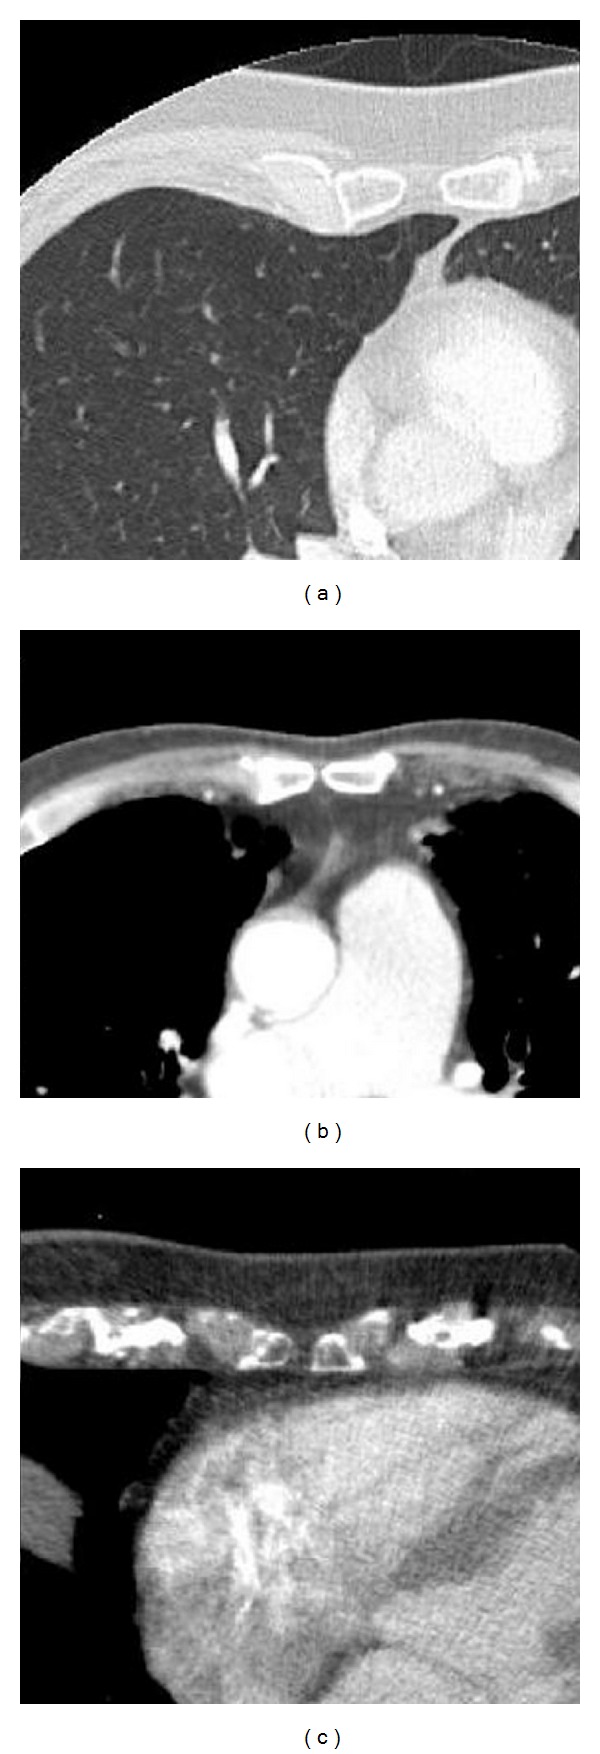

胸骨孔是一种众所周知的胸骨变异解剖结构,具有危及生命的并发症的风险,如气胸,甚至在胸骨活检或针灸时心包/心包穿刺。已经有大量的研究对胸骨孔的患病率进行了大量的研究,但对胸骨孔与胸内结构的确切解剖关系的研究却很少受到关注。在回顾性研究15例胸骨孔患者,地形解剖方面的胸部重要器官进行了检查。大多数患者的直接邻近结构为肺(53.3%)或纵隔脂肪(33.3%)。只有3例患者心脏位于胸骨孔附近(20%)。从理论上讲,如果针头插入足够深,所有被检查的患者都会在某一点穿穿心包。患者的体质(即皮下脂肪的厚度)与到重要器官的距离之间没有相关性。在本例中,如果针的插入深度不超过2.5 cm,就不会发生心包穿刺。鉴于数据的初步性质,对于针头深度安全阈值的一般结论应谨慎作出。为了尽量减少危险并发症的风险,特别是胸骨活检,建议术前筛查或图像指导。

Sternal foramina are a well-known variant anatomy of the sternum and carry the risk of life-threatening complications like pneumothorax or even pericardial/cardial punction during sternal biopsy or acupuncture. There have been numerous studies numerous studies examinimg prevalence of sternal foramina, but the study of the exact anatomical relationship to intrathoracic structures has received little attention. In a retrospective study of 15 patients with sternal foramina, the topographical anatomy in respect to vital chest organs was examined. In most patients, the directly adjacent structure was the lung (53.3%) or mediastinal fat (33.3%). Only in three patients, the heart was located directly adjacent to a sternal foramen (20%). Theoretically, if the needle is inserted deep enough it will at some point perforate the pericardium in all examined patients. There was no correlation between the patient habitus (i.e., thickness of the subcutaneous fat) and the distance to a vital organ. In this sample, pericardial punction would have not occured if the needle is not inserted deeper than 2.5 cm. Given the preliminary nature of the data, general conclusions of a safe threshold for needle depth should be made with caution. To minimize the risk of hazardous complications, especially with sternal biopsy, preprocedural screening or image guidance is advocated.